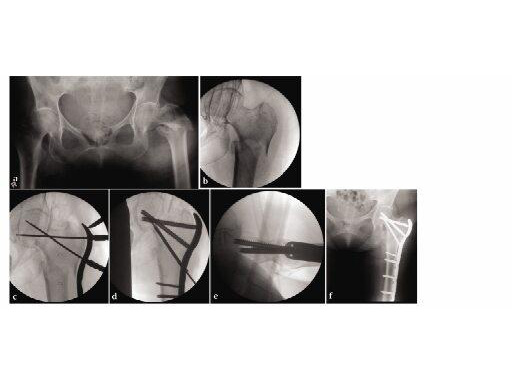

78-year-old osteoporotic female with a left subtrochanteric femur fracture. The proximal femur has a frontal plane fracture in it. Advantages include excellent purchase of the osteoporotic proximal segement, avoidance of abductor devitaliation, and reestablishment of the normal neck-shaft angle.